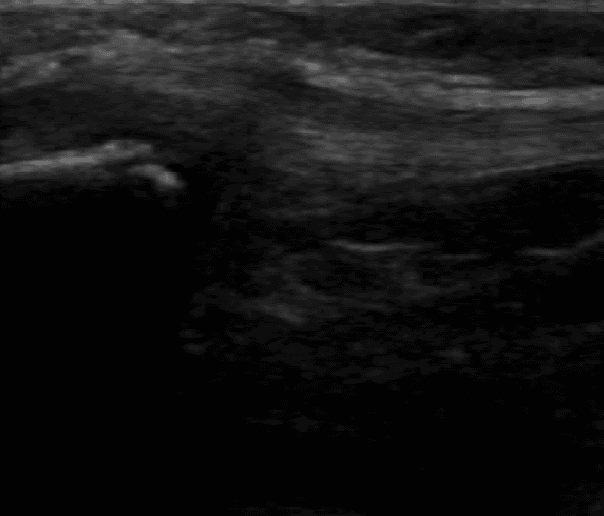

腫れはそこまで出ていなかったので、骨折か捻挫の判断をするためにエコー検査を行いました。

エコー検査では、右腓骨遠位端部に裂離骨折像が確認できたため、ギプス処置を施しました。ギプス固定でも、固定中に超音波骨折治療器(LIPUS)を行うために有窓ギプスにしました。LIPUSは週4〜5回照射(20分)行うことによって骨癒合期間が40%短縮されると報告されています。